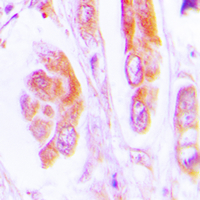

Immunohistochemical analysis of Caspase 7 staining in human lung cancer formalin fixed paraffin embedded tissue section. The section was pre-treated using heat mediated antigen retrieval with sodium citrate buffer (pH 6.0). The section was then incubated with the antibody at room temperature and detected using an HRP conjugated compact polymer system. DAB was used as the chromogen. The section was then counterstained with haematoxylin and mounted with DPX.